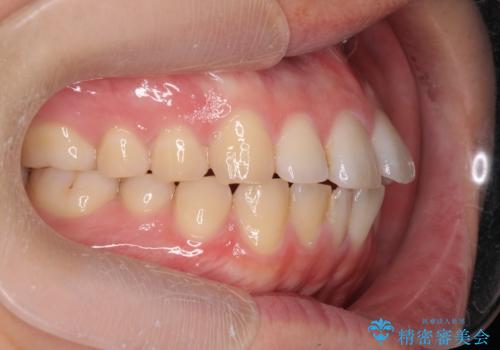

前歯が気になる。インビザラインライト

- 前歯が気になるとの事で来院。

矯正を希望されたが費用と時間を抑えたいとの事でインビザラインライトで矯正を行いました。(奥歯の位置関係はほぼ変えない)

前歯が綺麗に並び大変満足して頂けました。